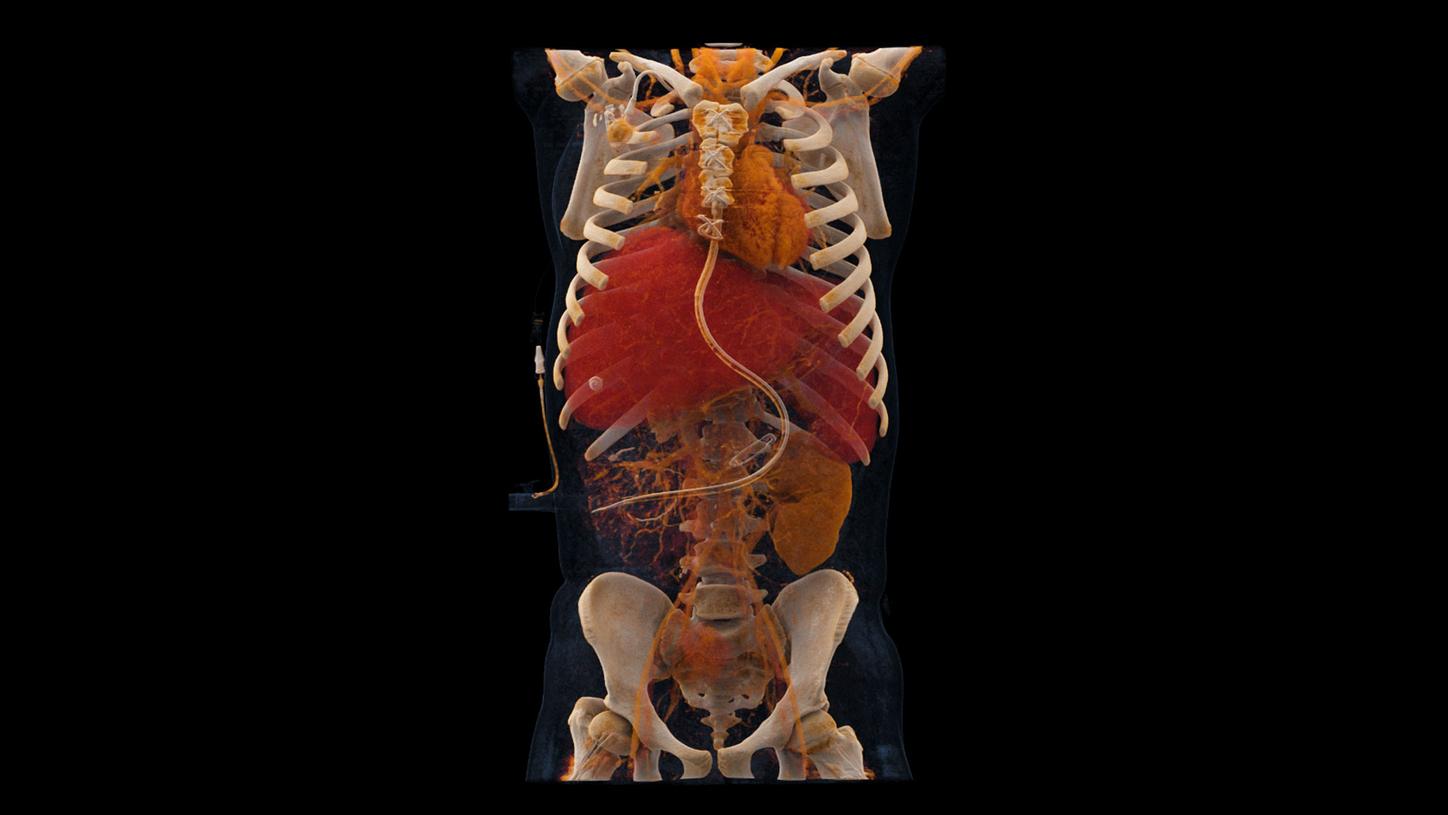

In 2021, NAEOTOM Alpha® with Quantum Technology was the first photon-counting CT in clinical use. And now, the next generation has arrived: NAEOTOM® Alpha.Peak debuts with the proven technology of the original as the pinnacle of the NAEOTOM Alpha class. Explore the evolution.

NAEOTOM Alpha with Quantum Technology, the world's first photon-counting CT, marked the beginning of the photon-counting CT era. Its never-seen before technology is designed to guide therapeutic and clinical decision-making for more patients.

At the heart of NAEOTOM Alpha® is a radically new photon-counting detector. The QuantaMax detector directly converts X-rays into an electrical signal, which is then used to create an image. The energy of each X-ray is measured, so spectral information is available for every scan, and the images are contrast-rich with high spatial resolution at the same dose. Combining the high spatial resolution of the QuantaMax photon-counting detector with our Dual Source temporal resolution enables the visualization of fine details for increased diagnostic confidence.